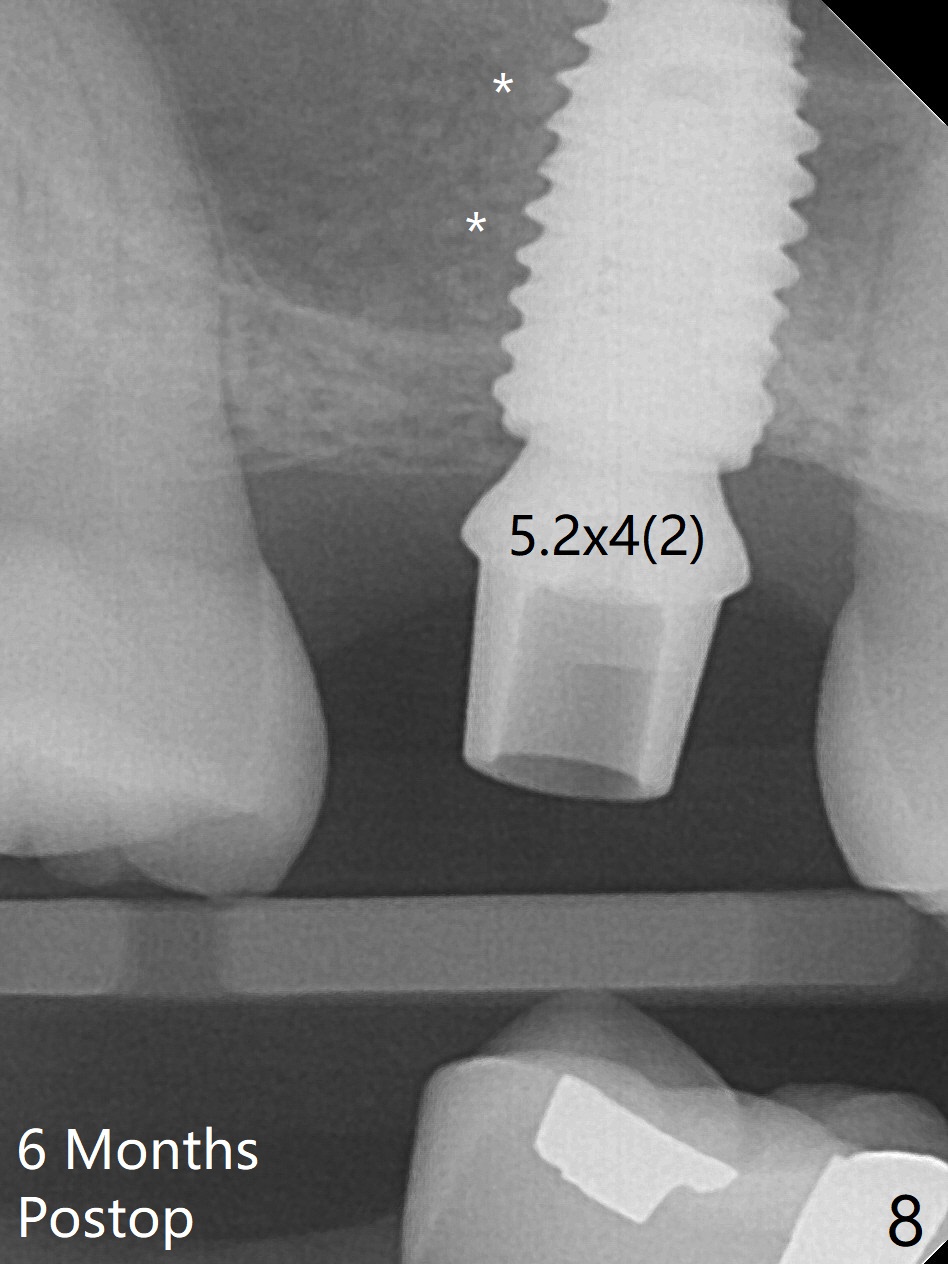

When the residual roots of the tooth #3 are removed, there is a gingival band over the septum (Fig.1 S). Osteotomy (Fig.2 yellow circle) would tear it off. To save the soft tissue, the buccal attachment is severed (Fig.3 black line), the flap is rotated palatal (Fig.3 curved arrow) and sutured in place (Fig.5 S). After sinus floor breakdown (use of sinus drill for 16 mm) and use of membrane lifter/water, two pieces of PRF membrane are inserted. The membrane is so slippery that it is easy to enter the sinus for further sinus membrane lift and later allograft placement (Fig.4 *). A 4.5x10 mm dummy implant is placed with high torque after 4x7.3 mm drill with 3 mm stopper so that 4.5x7.3 mm drill with 1 mm stopper is used before placement of a 5x8.5 mm final implant with ~ 35 Ncm (Fig.5-7). The patient reports anterior sinus wall tenderness with right nasal discharge a few days postop. The provisional has mobility without tenderness 1 week postop. It appears that the sinus membrane has been involved, which is quickly repaired probably by PRF. There is no pain when a 5.2x4(2) mm cemented abutment is torqued at 30-35 Ncm before impression (Fig.8). The surrounding soft tissue is healthy. When the permanent crown is delivered, the patient feels light pain when she bites hard. The discomfort persists 4 months post cementation (Fig.9). The crown/abutment is replaced with a healing abutment (Fig.10). There is no bone loss 4 months post healing abutment placement (14 months post implant placement, Fig.11). Upper Molar Immediate Implant, Prevent Molar Periimplantitis (Protocols, Table), Trajectory II, 31 Flap Not Transferred Xin Wei, DDS, PhD, MS 1st edition 07/26/2019, last revision 10/05/2020